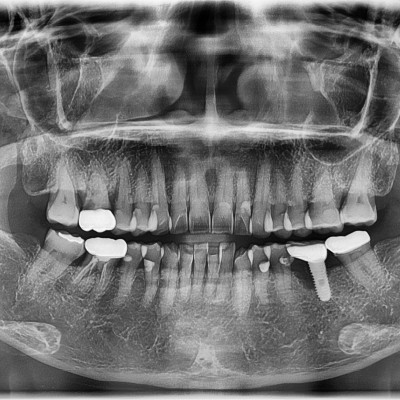

임플란트 재수술 #24.25 타원임플란트 제거 후 임플란트 재수술 + 치조골 이식술 시행하였습니다.

작성자 이턱이 작성일 01-27 조회 128